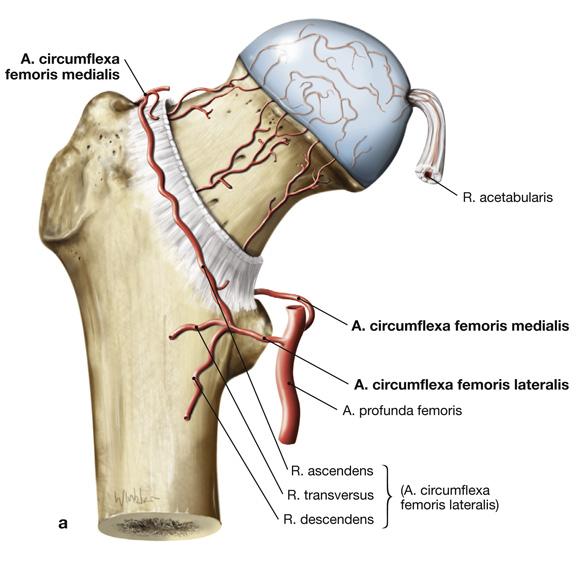

Fig 3.29b1: Details - femur